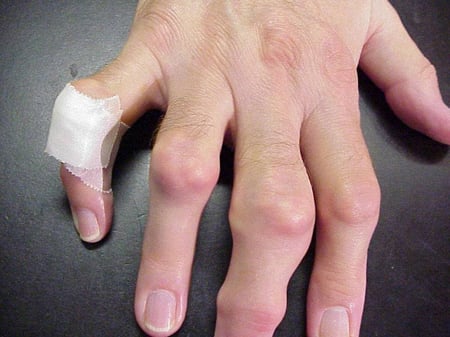

Gout flares can occur in joints that look normal, or in joints that have easily visible deposits of uric acid. These deposits are called tophi (See Figures: 7a and 7b: Tophi on Foot and Over Achilles' Tendon, Figure 8: Tophus on Elbow, Figure 9: Tophi on Hands, and Figure 10: Large Tophus of Finger) and can be in numerous locations, but especially on the feet and elbows. In Figure 9, the little finger of the right hand is bandaged since fluid was just removed from it, which demonstrated innumerable uric acid crystals.

Photo showing tophi on hands

Figure 9: Tophi on Hands